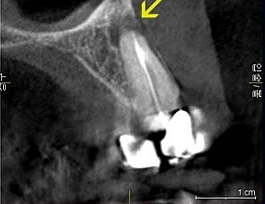

下の画像をご覧ください。

左の画像が2次元のレントゲンで、右が3次元のCT画像です。

矢印の所にバイ菌が入って居るのですが、CT画像の方がはっきりとバイ菌の居場所がわかる為、治療が成功しやすいです。

▲ 普通の歯科用レントゲン写真

▲ CT撮影で立体的に見た写真